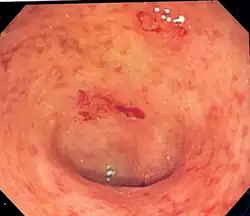

Wrzodziejące zapalenie jelita grubego (łac. colitis ulcerosa, CU), zaliczane do grupy nieswoistych zapaleń jelit, jest przewlekłym procesem zapalnym błony śluzowej odbytu lub jelita grubego o nieustalonej dotychczas etiologii.

Choroba charakteryzuje się występowaniem zaostrzeń i okresów remisji o różnym okresie trwania. Najczęściej obejmuje końcową (lewą) część jelita grubego – odbytnicę (która zajęta jest w 95% przypadków), esicę, okrężnicę zstępującą, zagięcie śledzionowe. Rzadziej zajmuje całe jelito grube, aż do zastawki krętniczo-kątniczej. Nigdy nie dotyka bezpośrednio jelita cienkiego. Jedynym objawem może być tzw. backwash ileitis, który występuje w momencie zajęcia jelita grubego na całej długości (pancolitis) wraz z zastawką krętniczo-kątniczą, która staje się niewydolna i przepuszcza mediatory procesu zapalnego w kierunku końcowych odcinków jelita krętego. W odróżnieniu od choroby Leśniowskiego-Crohna we wrzodziejącym zapaleniu jelita grubego istnieje znacznie mniejsza tendencja do powstawania przetok okołoodbytniczych, ropni i perforacji jelit. Występuje natomiast większe prawdopodobieństwo powstania raka jelita grubego. Skłania to do wykonywania regularnych kolonoskopii diagnostycznych u osób długotrwale chorujących na wrzodziejące zapalenie jelita grubego. Ze względu na zajęcie przez chorobę dystalnej części odbytnicy dużą wartość diagnostyczną ma również wykonanie rektoskopii.

- badania endoskopowe jelita grubego – rektoskopia, kolonoskopia, z pobraniem wycinków do badań histopatologicznych;